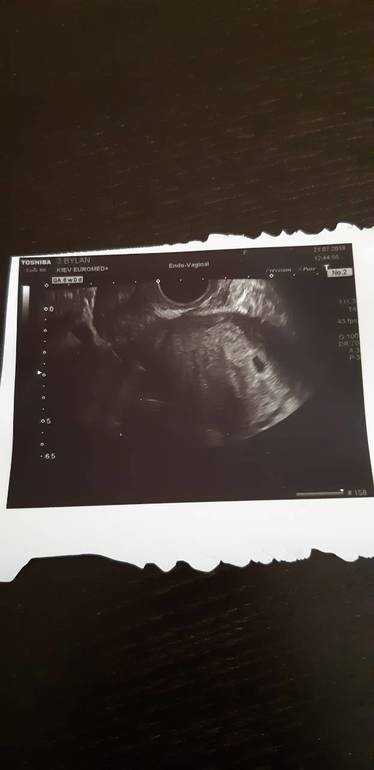

УЗИ, КТГ, доплерВобщем вся такая веселая прискакала я на узд. Начинается осмотр, на против меня висит плазма, чтоб я видила весь процес.Смотрит она смотрит , ну конечно смотрю и я и понимаю что я ничего не вижу. Так она смотрела мин 2 даже переспросила по поводу теста у меня. Я уже думала все, это конец. И тут что-то мелькнуло...и.... есть😊 есть пя в матке.О Боже, я была на седьмом небе от счастья 😆ПЯ 6.7ммКтр 3.5 мм живой.Сердцебиение есть но плохо прослушивается из-за маленького срока.Б соответствует 6 неделям😆ШМ 42мВобщем сказала через две недели повторно на узд, будем слушать сердечко 😊Я довольна как слон😆А вот наша первая фотография 😃Моя бусинка, мое малюсенькое счастье)